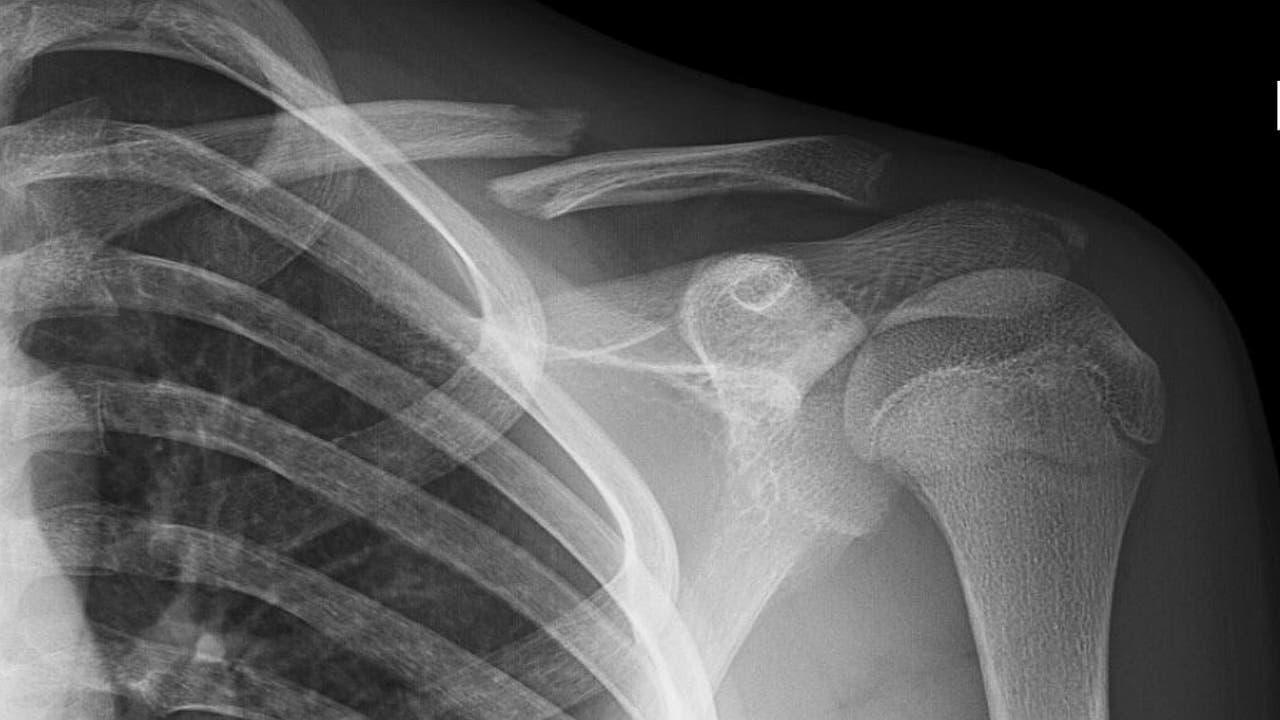

¿Se opera o no se opera una fractura de clavícula?